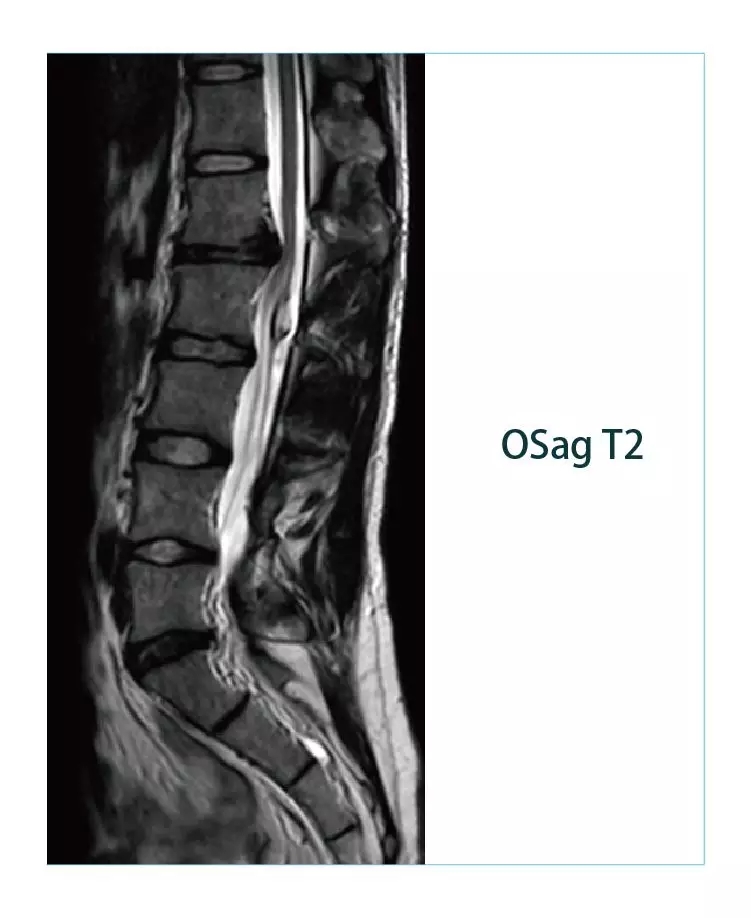

【朗润影像档案】20190225磁共振影像病例结果讨论